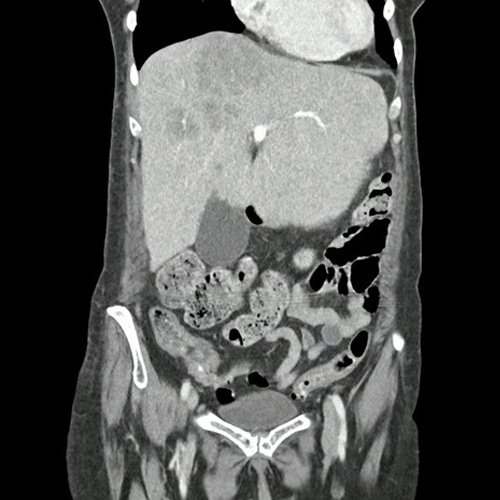

• TAC tórax (un mes atrás):La porción visualizada de la glándula tiroides es de características normales. Las estructuras vasculares paraaórticas son de características normales, permeables. La aorta ascendente, el cayado y la aorta descendente son de calibre y trayectoria conservados. Las estructuras venosas mediastinales: vena cava superior, vena cava inferior, venas pulmonares superiores e inferiores y venas ácigo-hemiácigos, son de calibre y trayecto conservado. La arteria pulmonar y sus ramas son de calibre y trayecto conservados.. Relación aórtico-pulmonar conservada. El corazón es de tamaño normal. El pericardio es de espesor conservado. El esófago es de calibre y trayecto normales. El mediastino está en posición central. Estructuras ganglionares pre y laterotraqueales, subcarinales, axilares bilaterales, aumentadas en número y de tamaño, algunas de ellas de rango megálico, destacándose una axilar izquierda con pérdida de la morfología habitual que mide 10 mm en su eje corto.

• TAC de tórax sin contraste - informe preeliminar (Dia 31):  Estudio artefactado por movimientos respiratorios de la paciente. Se observan múltiples lesiones nodulares sólidas, irregulares, heterogéneas, que se extienden por ambos campos pulmonares a predominio derecho, de manera periférica y subpleurales, asociadas a vidrio esmerilado, destacándose la de mayor tamaño en segmento lingular inferior que mide 12 mm x 16mm. Hallazgos que podrían corresponder en primera instancia a proceso inflamatorio infeccioso sin poder descartar secundarismo. Se sugiere control evolutivo.  Hallazgos no visualizados en Tc del día 05-08-2025, si se observan en TC del día 24-09-2025. Bulla subpleural paramediastinal, de 14mm, en segmento posterior del LSI. Leve derrame pleural, en esta ocasión, bilateral, de mayor jerarquía a derecha. Múltiples estructuras ganglionares pre y lateroaórticas, axilares bilaterales aumentada en número y de tamaño, de rango no megálico. Laminar derrame pericárdico.

TAC de tórax (internación previa)